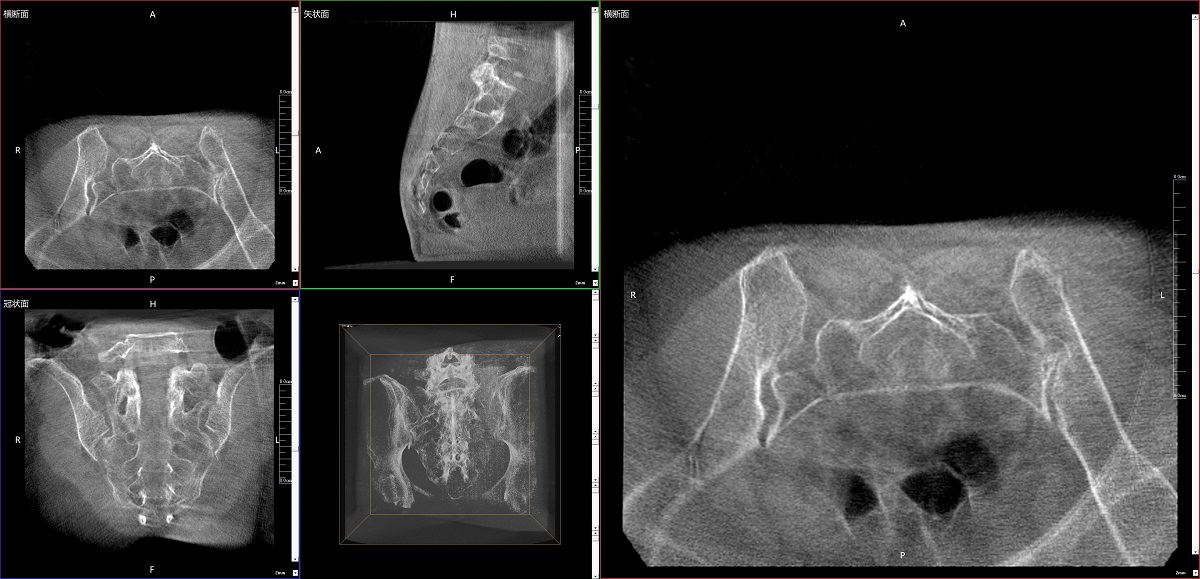

在骨科手術(shù)中,影像相當于醫(yī)生的“眼睛”,要先“看得清",才能“算得準” “打得穩(wěn)”。普愛醫(yī)療第三代平板三維C形臂協(xié)同醫(yī)院創(chuàng)傷導(dǎo)航機器人已開展多例“骨盆骨折微創(chuàng)手術(shù)”,成為上海市第七人民醫(yī)院手術(shù)技術(shù)創(chuàng)新的一大亮點。

普愛醫(yī)療第三代平板三維C形臂出色的二維透視和術(shù)中三維成像效果,為機器人提供了精確的術(shù)中影像依據(jù),協(xié)同提升手術(shù)整體的精準度和效率,為患者帶來了更安全、更高效的醫(yī)療服務(wù)體驗。